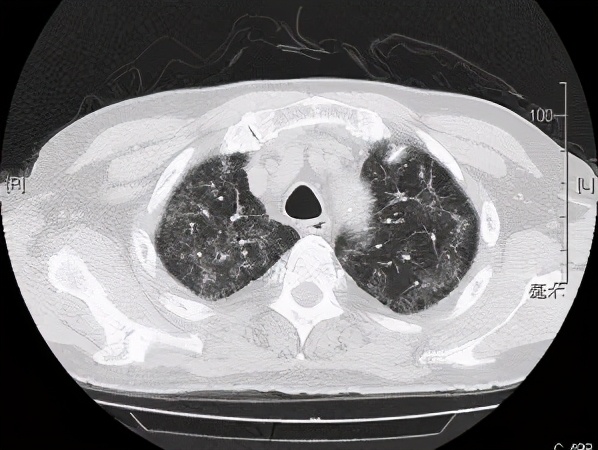

本院胸部CT(2019-08-30)示: 双肺弥漫性间质性改变,有网格状改变、毛玻璃影、局部有支气管牵拉形成支气管扩张的表现。

追溯患者2018年体检胸部CT(2018-1-22) :两肺下叶轻度间质增生,无显著双肺弥漫性间质改变。而且近一个月出现气促症状、低氧血症,说明间质性病变有活动性。